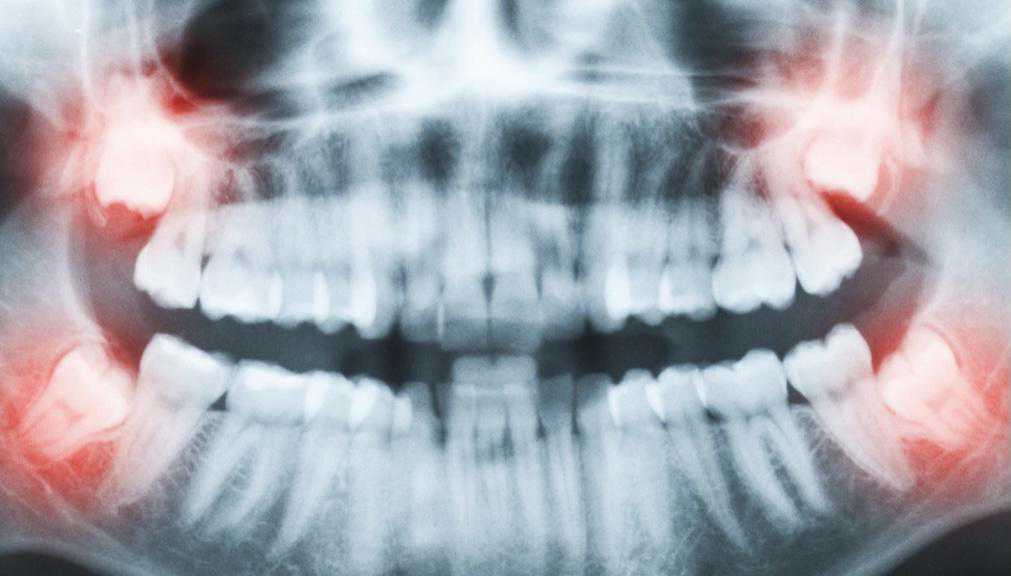

③拔除斜长、横长或埋在骨头里的下颌智齿,难度系数:★★★★

其实,这些就是我们俗称的阻生牙。

这一类智齿比较难拔,基本上都是微创手术了,但也需要切开牙龈操作,手术难度还是不低的。因此价格相比前两种手术会高一些。

拔牙前拍X光片可以让医生看到肉眼看不到的牙根形态、生长状态。

根据X光片的结果,医生可以更全面地评估拔牙的难度,定制拔牙的方案,向患者更好地解释一些可能存在的风险。

(面部肿胀、疼痛严重者随时复诊)